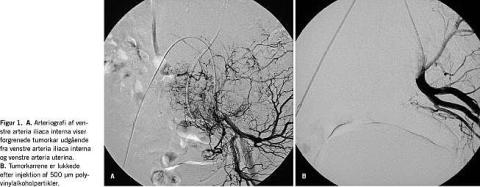

Ved en magnetisk resonans (MR)-skanning blev der fundet en velvaskulariseret tumor i venstre side tæt på arteria iliaca interna og externa. En angiografi viste, at den dominerende karforsyning udgik fra venstre arteria iliaca interna og arteria uterina. For at mindske den peroperative blødning blev der foretaget præoperativt embolisering af hovedstammerne til tumoren (Figur 1).

Præoperativ embolisering af tumoren kan reducere det intraoperative blodtab væsentligt. Dette er påvist især ved små sarkomer på ekstremiteterne [2]. I dette tilfælde blev der gennemført angiografi for at synliggøre fødekarrene med efterfølgende selektiv kateterisering af disse og embolisering med polyvinylalkoholpartikler (PVA), hvilket kun er beskrevet sporadisk i litteraturen.